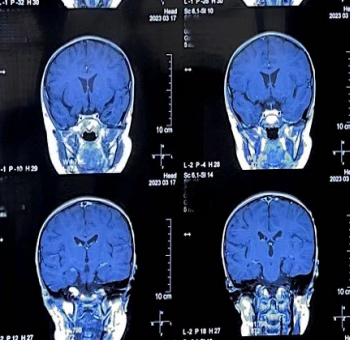

头部MRI检查(2023.03.17):

左侧蝶骨大翼区及邻近颞叶未见异常强化,提示达到完全缓解(CR)。

头部MRI增强(2024.06、2026.01):

未见明显异常。